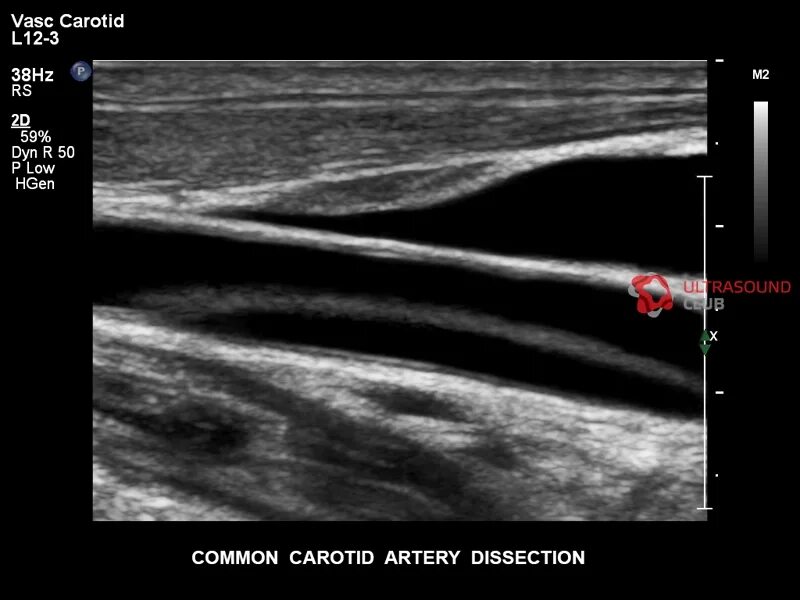

Сделать узи сонной артерии